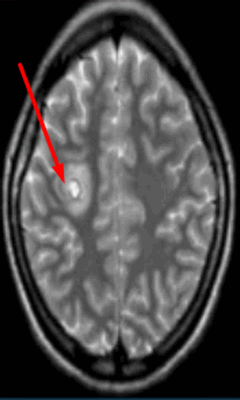

Очаг демиелинизации на МРТ